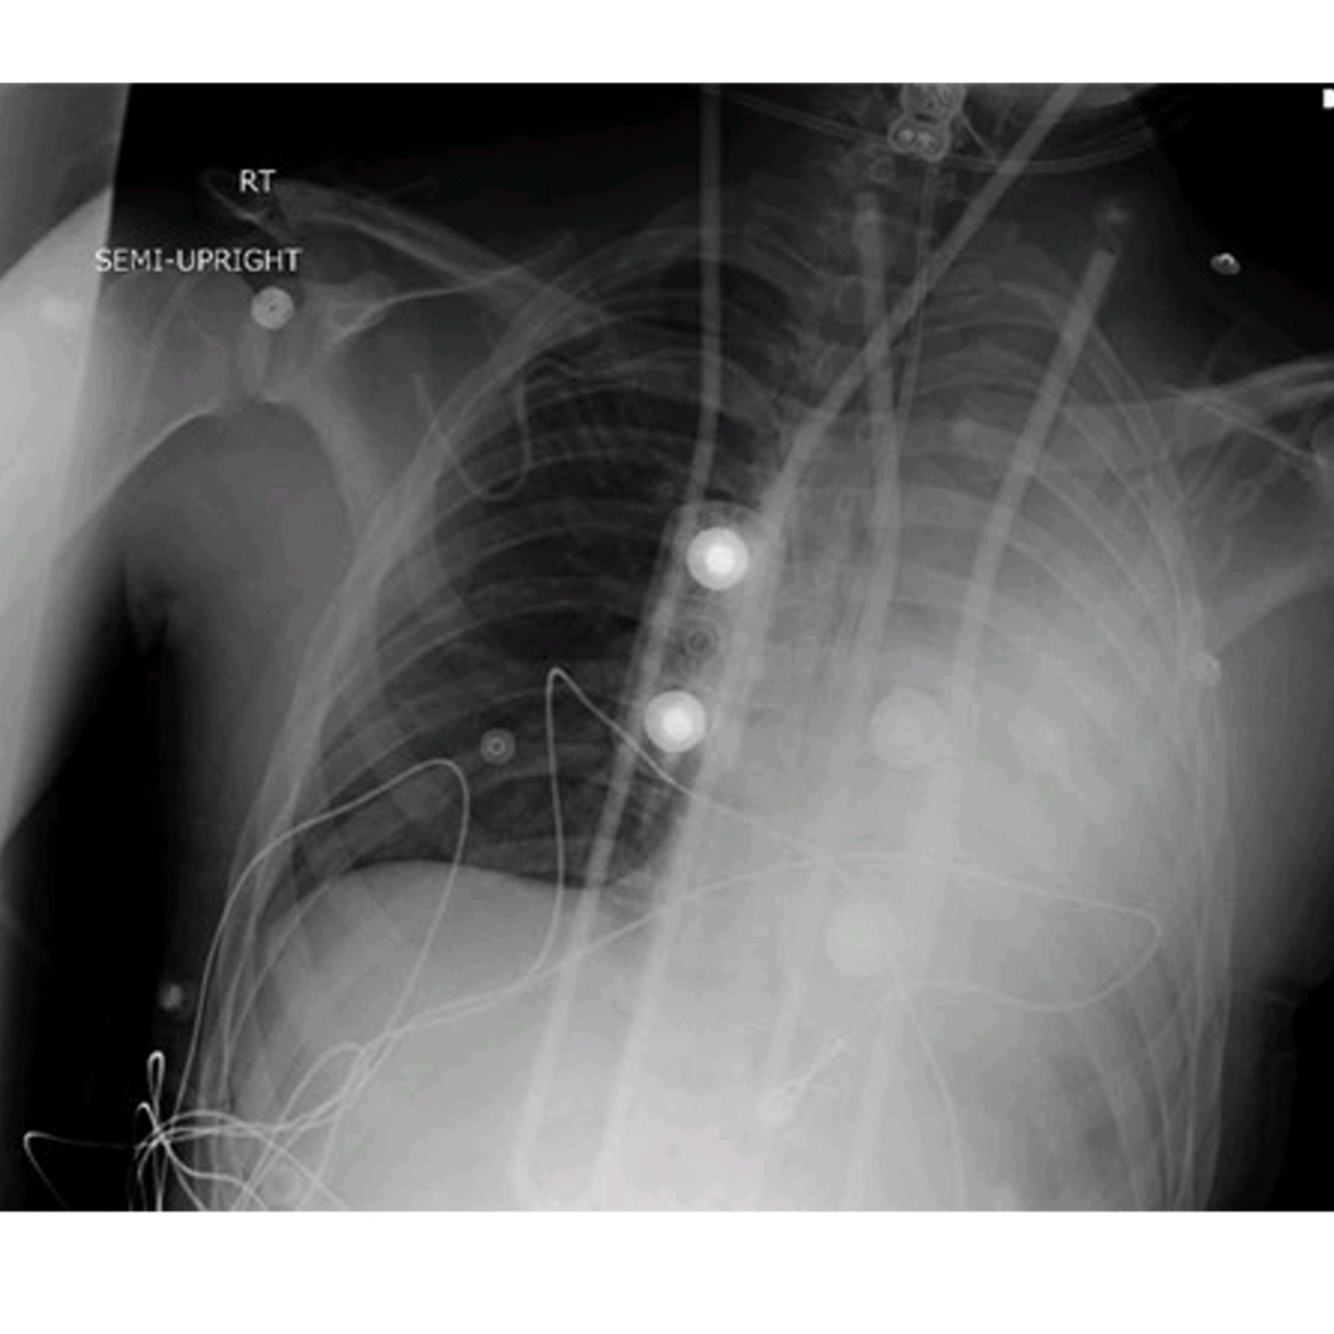

A 65-year-old female after a motor vehicle collision requires emergency surgery for an open lower extremity fracture; the patient tells you she has a “bad heart,” she has no history in your institution, and no signs of heart failure. An EKG shows wide QRS with dual-chamber pacing. A CXR on admission show (See Fig.46.1). 1. What type of device is shown in the image?

This patient has an implantable biventricular cardio-defibrillator (BiV ICD) [1].

(a) The radiographic image of a pacemaker would show (See Fig.46.2):

• Smaller generator

• Discreet right ventricular lead (stable diameter)

• With or without right atrial lead or coronary sinus lead

(b) The radiographic image of an ICD would show above image:

• Larger generator.

• Prominent right ventricular lead, otherwise known as shock coils.

They appear as two metallic segments along the length of the ICD lead.

(c) The radiographic image of a BiV ICD would show (See Fig.46.4):

• Larger generator

• Prominent right ventricular lead (shock coils)

• Right atrium lead

• Coronary sinus lead

Manufacturer ID can be seen in the CXR as well